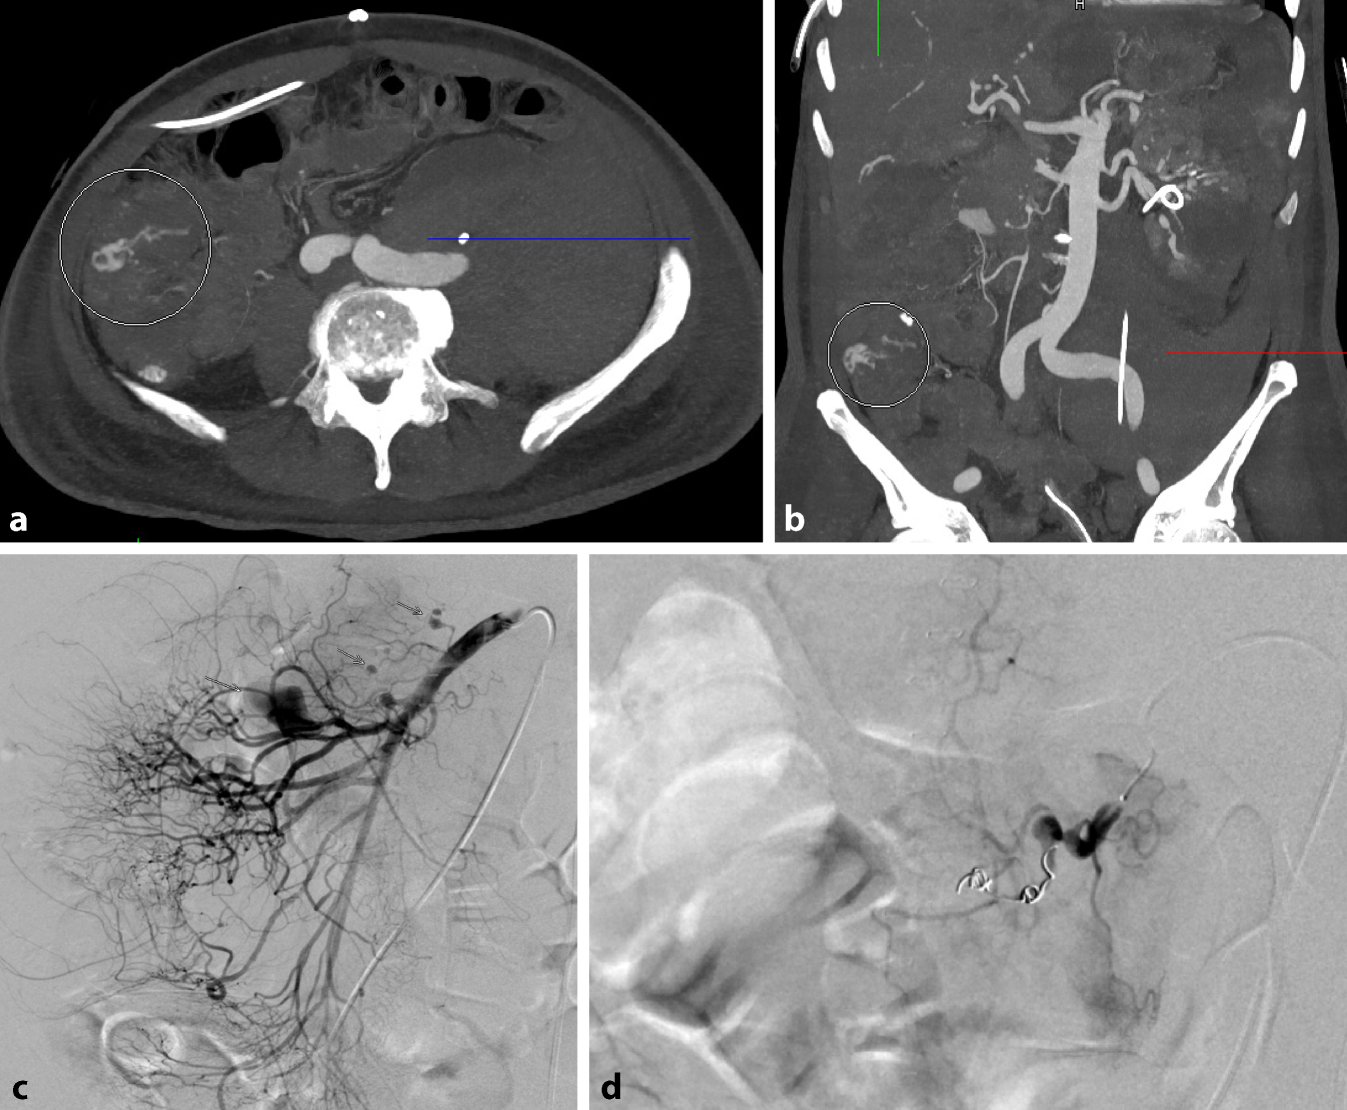

Hier berichten wir über einen zuvor gesunden normalgewichtigen 55-jährigen Mann, der sich mit Fieber bis zu 40 °C, trockenem Husten mit wenig Auswurf und Nachtschweiß vorstellte. Der Nachweis von Lungeninfiltraten im Röntgenbild des Thorax veranlassten den Hausarzt zur Verabreichung von Amoxicillin (p.o. 1 g 2 ×/Tag). Nach 4 Tagen wurde der Patient wegen anhaltenden Fiebers, Nachtschweiß und Holozephalgie mit Photophobie in unser Krankenhaus eingeliefert. Im Liquor wurden keine pathologischen Befunde festgestellt. In der routinemäßigen Blutkontrolle waren die Entzündungsparameter deutlich erhöht mit einem CRP von initial 366 mg/L, im Verlauf persistierend bei 238 mg/Lund einer BSR von > 130 mm/h mit deutlicher Leukozytose (Lc 22,2 G/L), Thrombozytose (Tc 661 G/L) und normochromer normozytärer Anämie (Hb 90–100 g/L). Das Procalcitonin (1,45 μg/L) war nur leichtgradig erhöht bei deutlich erhöhtem Ferritin (2674 μg/L). In der CT des Thorax zeigten sich anhaltende bilaterale Infiltrate mit Konsolidation im Oberlappen links und hilomediastinaler Lymphadenopathie. Die perorale antibiotische Therapie wurde zunächst auf intravenös Amoxicillin/Clavulansäure 2,2 g 3 ×/Tag umgestellt und Azithromycin 500 mg/Tag ergänzt, ohne Einfluss auf den klinischen Verlauf mit täglichen Fieberspitzen bis 39–40 °C mit Schüttelfrost. Nebenbefundlich fiel eine zunehmende Anämie (von Hb 107 g/L auf Hb 82 g/L) sowie eine Proteinurie (1,09 g/Tag ohne Erythrozyturie) auf. In einer FDG-PET-CT zeigte sich kein Hinweis auf eine Abszessbildung, Tumor, Lymphom oder Vaskulitis der großen Gefäße. Es wurde jedoch eine leichte FDG-Aufnahme in der Lunge festgestellt (Abb. 1). Auch die Autoantikörperdiagnostik war nicht wegweisend (Tab. 2).

Abb. 1

FDG-PET-CT in der koronaren (a) und axialen Schichtung (bd). FDG-Mehrbelegung in der rechten Lungenspitze am Ort eines umschriebenen Infiltrats (b, d)